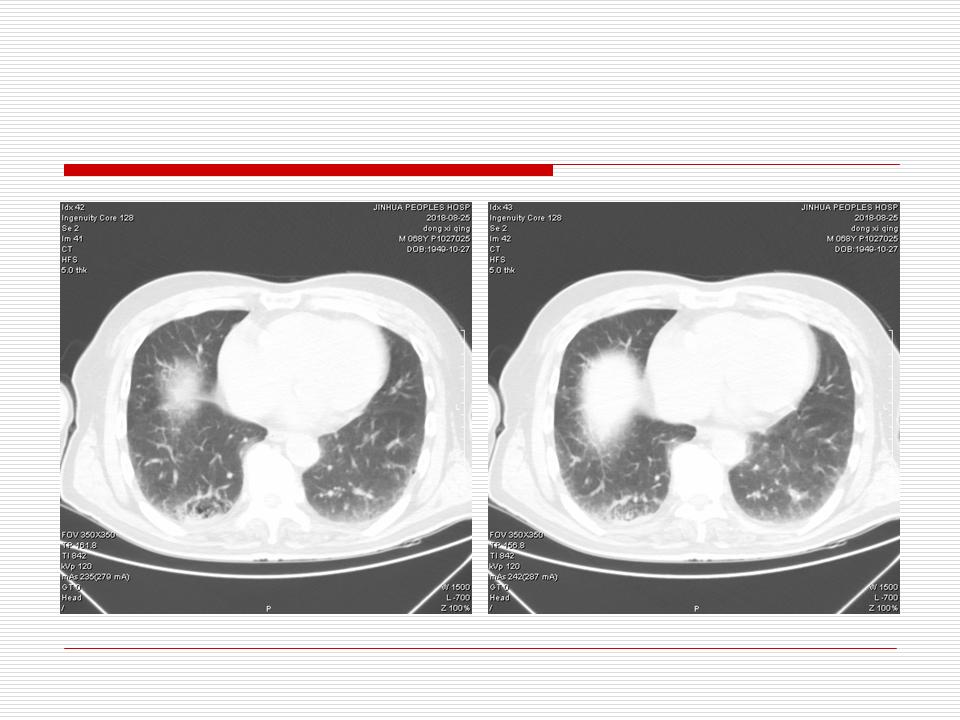

肺部阴影永恒且最重需要鉴别的是:到底是炎症还是肿瘤?但临床的病例中的影像表现难以界定或有些肿瘤特征,同时又有些炎症特点是非常常见的情况。作为临床医生我们怎么去总结分析,并找到之所以是炎症或之所以是肿瘤的细微差别或特点非常重要,也非常有用。2019.12.7浙江省2019年胸心外科学学术年会在宁波召开时,我的临床病例分析与经验总结<那些像肺癌的炎症与像炎症的肺癌>获得在大会交流的机会,以下为该PPT的内容,与你分享,希望对同道有益,有借鉴与启迪。若有探讨与进一不完善的建议,欢迎文末留言讨论: